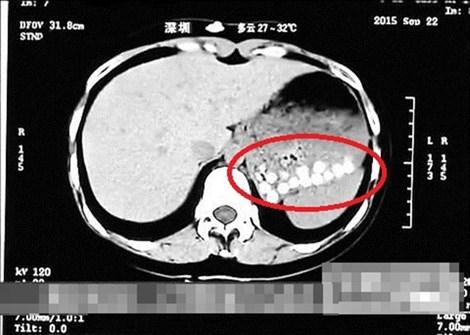

Đây là tuyên bố trong chương trình thường thức đời sống của đài này. Một PV tại Thanh Đảo cho biết đã uống trà sữa trân châu mua tại một cửa hàng địa phương sau đó chụp CT phần ổ bụng tại bệnh viện gần đó.Bản chụp CT cho thấy những hạt trân châu này không tiêu hóa được và nằm dồn lại trong dạ dày. Trung tâm Thí nghiệm hóa học của ĐH Thanh Đảo, các nhà hóa học đã lắc đầu khi không thể xác định chính xác hợp chất làm nên hạt trân châu; họ chỉ có thể xác nhận rằng đó là một "chất rất dính".